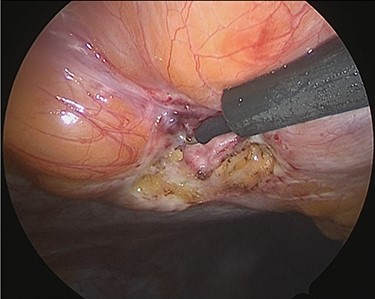

Under general anesthesia, with the patient in the lithotomy position, a 5-mm trocar was inserted into the lower right abdomen using the optical method. Observation of the abdominal cavity revealed a hernia orifice with a diameter of ~1 cm at the upper aspect of the umbilicus (Fig. 3). Two additional 5-mm trocars were inserted into the left side of the abdomen. The hernia sac was significant scarring. We then made an incision around the hernia orifice using a hook-type electrocautery electrode to expose the muscle layer (Fig. 4). The hernia sac was pushed from the surface of the body using a pean, inverted into the abdominal cavity, and excised as much as possible using electrocautery (Fig. 5). At that point, we employed the VersaOne™ Fascial Closure System to close the fascia and peritoneum at the port site.